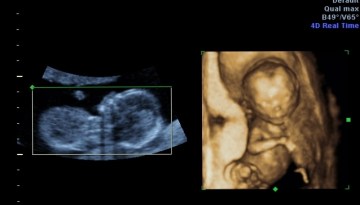

On this day a year ago I saw this sweet face up close for the first time. Her little button nose and tiny lips. Her cheek bones are defiantly mine and she looks like her big brother C.G. As I laid there with cold gel on my tummy I was mesmerized at her tiny features. Her little arms and legs were just so perfect. I could have laid there watching her for hours. I was there waiting to hear the words I’d been hoping and praying for…”It’s a GIRL!” Ahhh, thank you Lord! A precious daughter! A little sister to these two amazing boys! Tears streamed down my cheeks. My heart was full. The day was wonderful! All was right in the world!